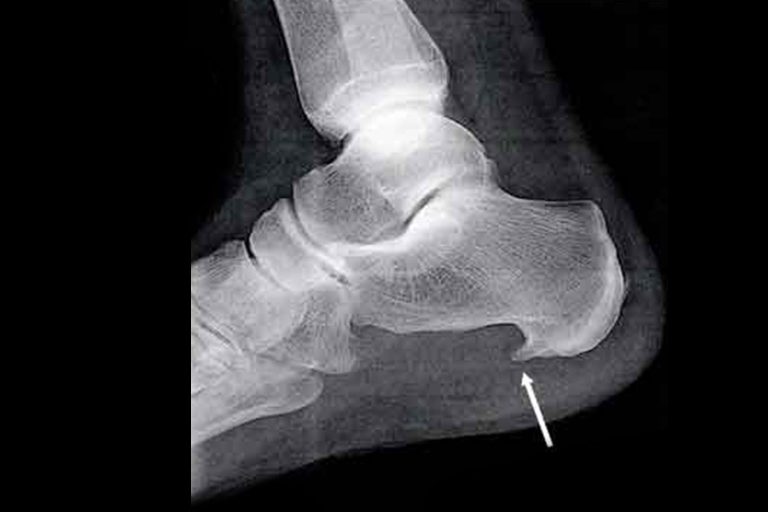

Tendinopathie : tout comprendre pour mieux guérir Une douleur persistante le long d’un tendon, qui s’aggrave à l’effort et refuse de disparaître au repos voilà souvent le premier signe d’une tendinopathie. Pourtant, ce mot recouvre des réalités très différentes selon…